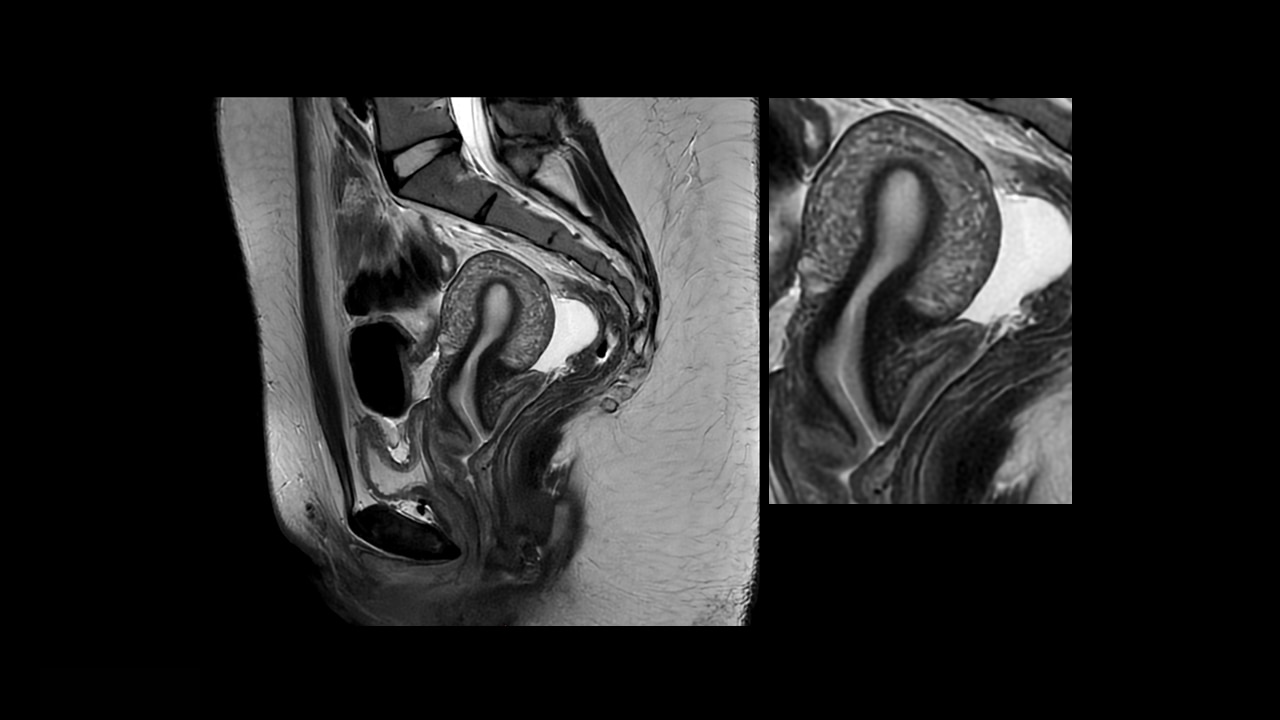

PROPELLER uses a radial k-space filling pattern that is inherently less sensitive to motion such as CSF and blood flow, breathing, patient tremor, or voluntary movements. The oversampling of the k-space center yields increased signal-to-noise ratio (SNR) and high tissue contrast. Scan time is the same as conventional techniques, and PROPELLER allows free-breathing acquisition.